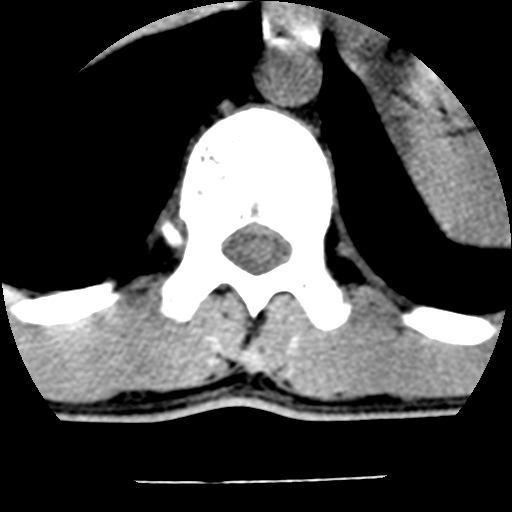

男,31岁,从6米高处坠落伤两天,腰背部疼痛,临床要求ct扫描胸10-腰1。请大家帮忙看看骨质有问题吗?

t12、l1锥体前缘轻度楔形变,平扫示椎体前缘骨小梁欠规整,第9幅图示椎体前缘骨质不连续,结合外伤史考虑椎体轻度压缩骨折。

楼主扫描层厚可能较大,每个椎体只有三个层面.

从所示层面分析,无明确骨折征象,象类似病人我个人会建议mri除外骨挫伤.

从上查骨窗第九片椎体前缘皮质显示断裂.压缩骨折?